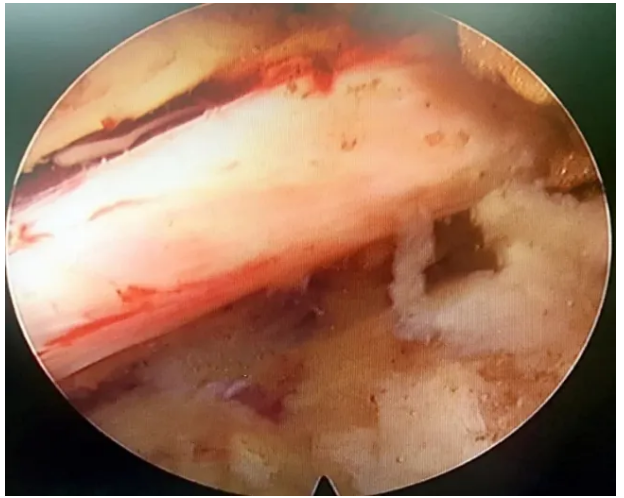

椎间孔镜手术进行中

经过对这名患者病情进行综合评估后,鉴于患者年龄较大,可能难以承受传统开放手术,五洲中医院手术团队建议患者行“椎间孔镜椎间盘髓核摘除术”,该手术较常规手术而言创伤小、出血少、恢复快。此次开展的椎间孔镜技术,不用开刀,在椎间孔镜可视的情况下可直接摘除突出的髓核。

经患者和家属同意后,于9日下午将近17时开始手术,手术在局部麻醉下完成手术,在内镜直视下清楚的看到突出的髓核、神经根、硬膜囊和增生的骨组织,切除突出的髓核松解神经粘连,扩大狭窄的椎管。整个手术过程张女士完全清醒,在髓核摘除的过程中,其手术创口小,术中出血仅5ml。